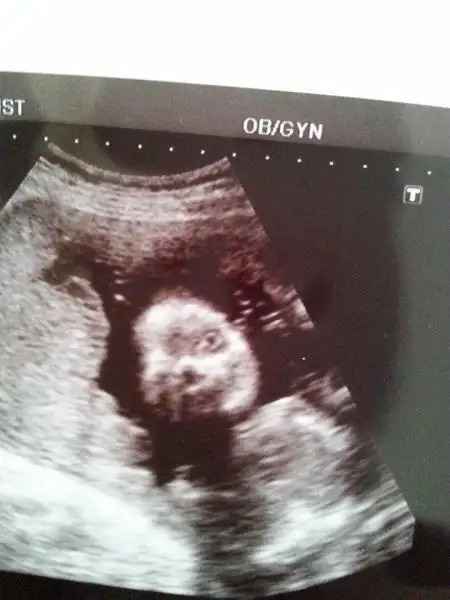

işte benim küçük kurbişiiim :16:

:nazar::nazar::nazar::nazar::nazar::nazar::nazar::nazar::nazar::nazar::nazar::nazar::nazar:

$DSCF4087.webp

$DSCF4098.webp